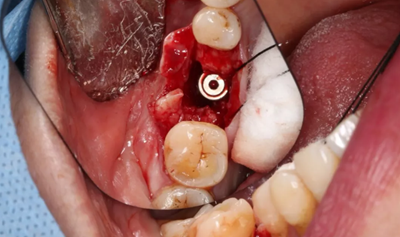

11、常規(guī)植入WEGO種植體一顆

牙槽嵴頂水平切口,翻瓣,牙槽嵴近中較遠(yuǎn)中豐滿(mǎn)。

(攝于2017年4月14日)

植入國(guó)產(chǎn)威高(WEGO)5.0×11mm種植體,檢查種植體位于理想軸位。